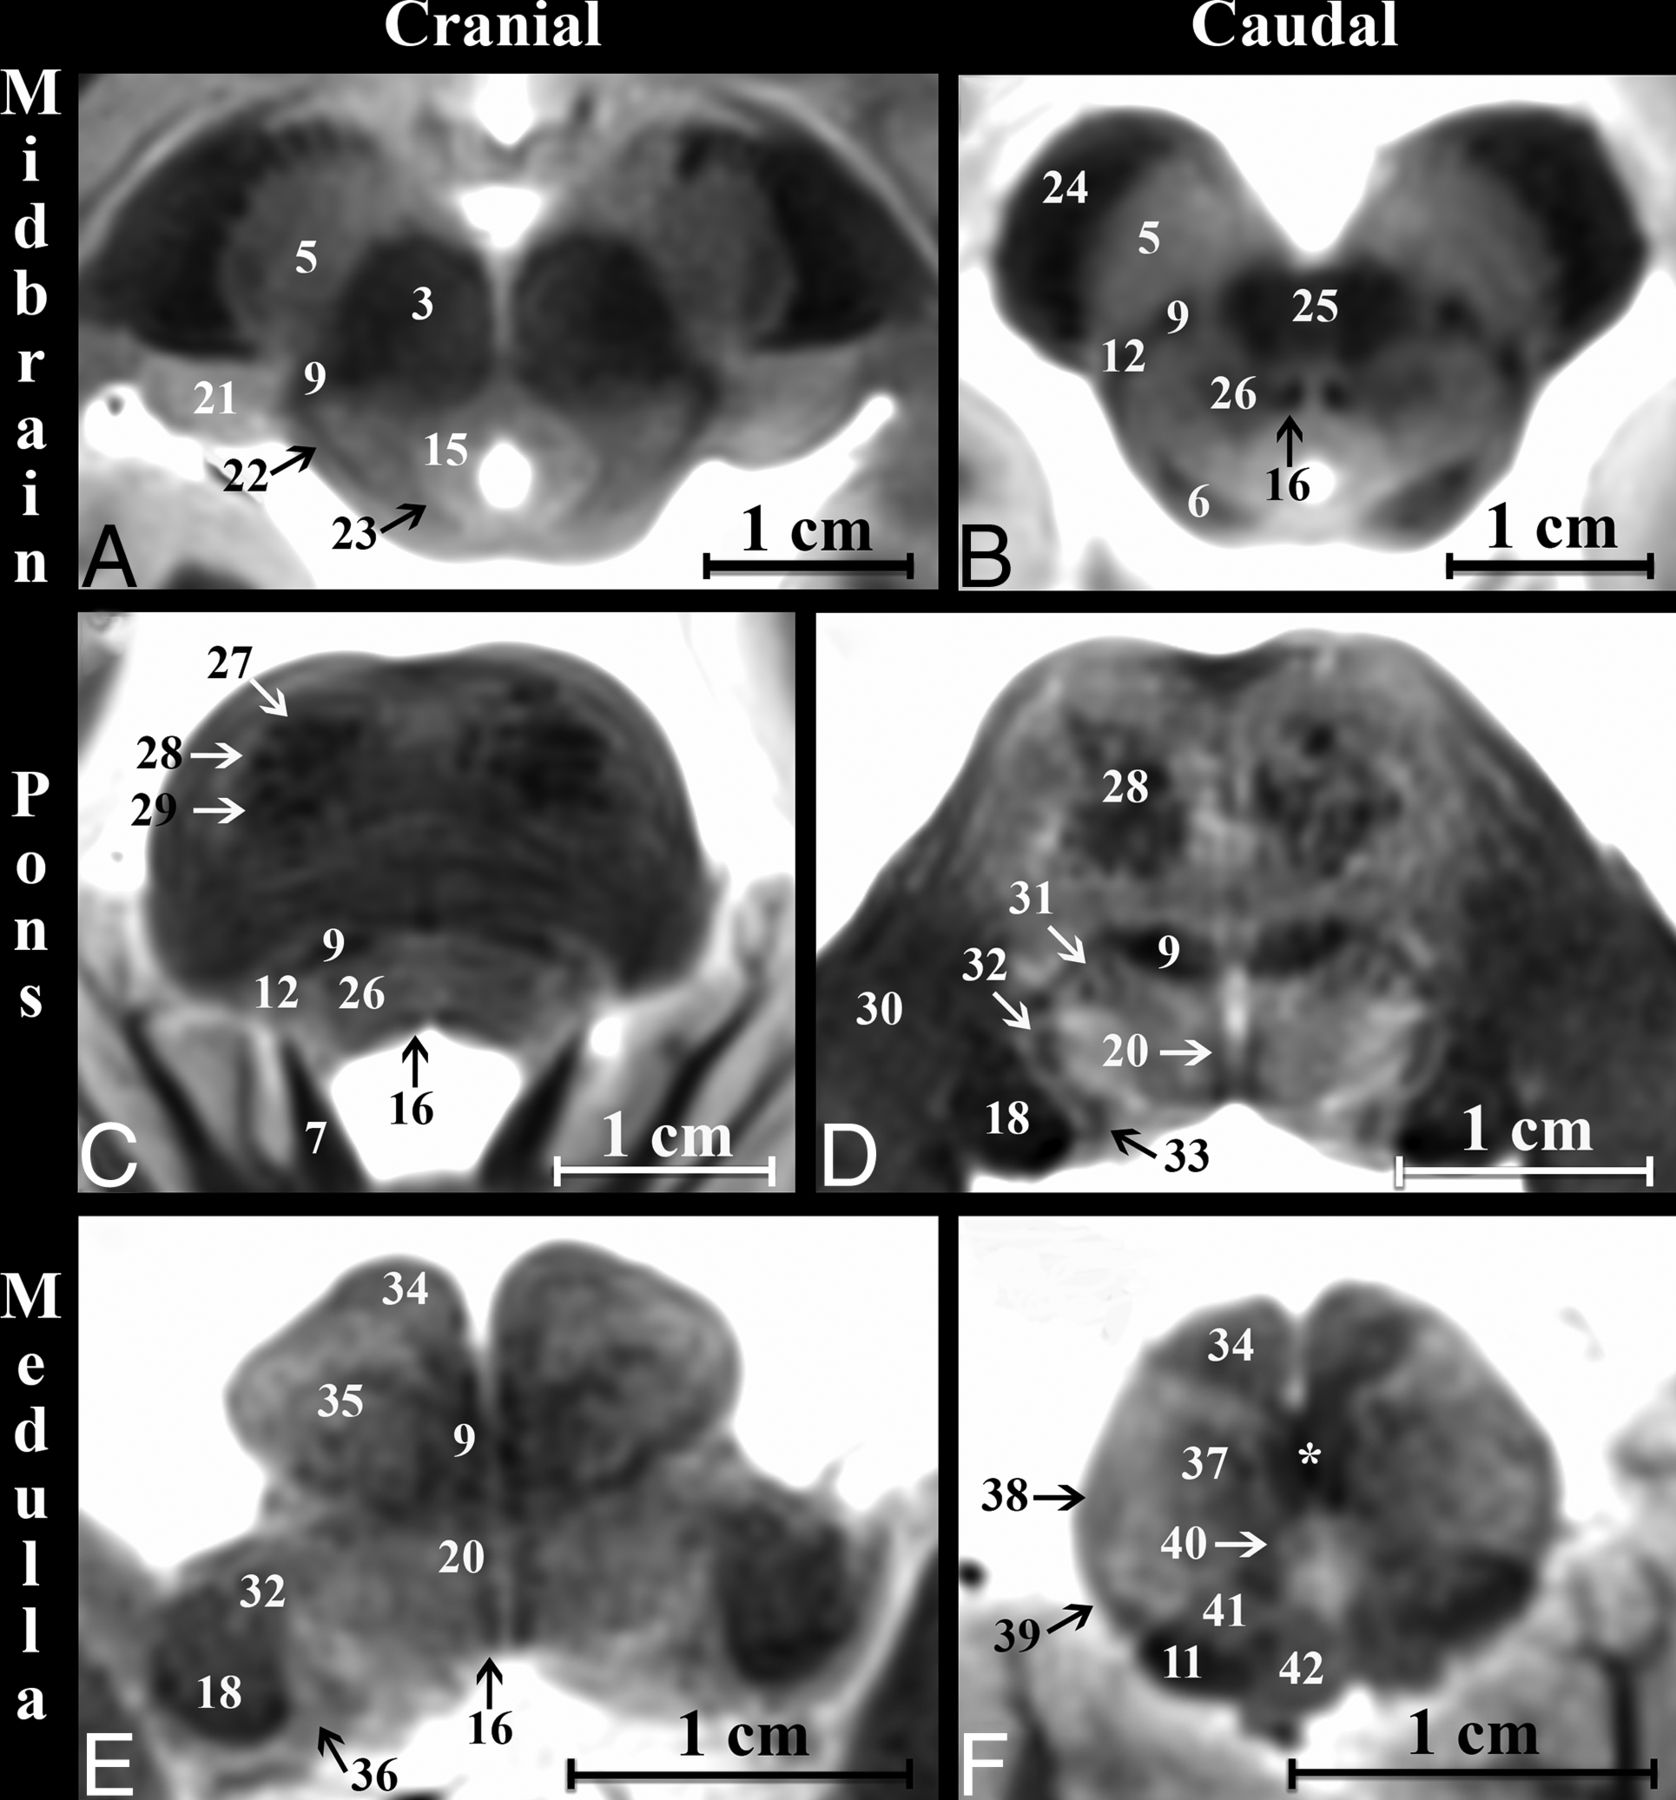

Axial modified T2-weighted TSE images at 6 canonical levels of the postmortem brain stem orientated parallel to the anterior/posterior commissure plane. Upper row: A, cranial midbrain; B, caudal midbrain. Middle row: C, cranial pons; D, caudal pons. Lower row: E, cranial medulla, F, caudal medulla. Improved image contrast from the modified TSE sequence directly demonstrates even small structures like the medial longitudinal fasciculus (16). Note the sensory decussation of the medial lemniscus in the caudal medulla (asterisk, F). The motor decussation is demonstrated in Fig 3.

We briefly describe the course, orientation, and shape of 5 major white matter pathways based on the 13 whole-brain specimens (all measurements are reported as mean ± SD). The numbers in parentheses refer to the numbers of the brain structures listed in the On-line Table. The corticospinal tract (28) (Fig 3) is the major motor pathway controlling the voluntary movements of the limbs and trunk. The CST at the midbrain level is 1.3 ± 0.1 cm lateral to the midsagittal plane and descends within the cerebral peduncle (24) from the posterior limb of the internal capsule at a 31° ± 7° angle from superolateral to inferomedial in the coronal plane. The center of the tract is 0.6 ± 0.05 cm deep to the ventral surface and 0.4 ± 0.09 cm lateral to the midsagittal plane at the midpons, while maintaining a rounded shape before converging fibers descend to the medullary pyramids (34) at a less steep superolateral-to-inferomedial 14° ± 2° angle. The pyramids form the ventral surface of the medulla and are 0.26 ± 0.04 cm lateral to the midsagittal plane. The CST descends at a 5° ± 2° anterosuperior-to-inferoposterior angle relative to the long axis of the brain stem in the sagittal plane. CST signal intensity remains T2-hypointense even with tract dispersion in the pontine levels (Fig 2).

After the internal arcuate fibers (37) decussate, the medial lemniscus (9) (Fig 4) is in the central paramedian medulla with an elongated ovoid shape and its long axis oriented anterior to posterior on axial images. The ML is a sensory pathway conveying fine touch, vibration, and proprioception of the skin and joints. As the ML ascends, its long axis rotates at 56° ± 11°, 80° ± 9°, 115° ± 13°, and 130° ± 4° angles relative to the midsagittal plane at the caudal pons, middle pons, cranial pons, and caudal midbrain levels, respectively. The tract is located 0.3 ± 0.05 cm and 0.8 ± 0.06 cm lateral to the midsagittal plane at the pons and midbrain levels, respectively. In the sagittal plane, the ML ascends at a 4° ± 1° anteroinferior-to-posterosuperior angle relative to the long axis of the brain stem at the medulla but pivots posteriorly 18° ± 5° at the pontomedullary junction and pivots again posteriorly 17° ± 3° at the midbrain. The ML maintains uniform signal intensity until the fibers become less distinct just before terminating in the ventral posterolateral thalamic nucleus (50).

The medial longitudinal fasciculus (16) (Fig 5) is a small tear drop–shaped tract just deep to the rhomboid fossa, 0.05 ± 0.01 cm lateral to the midsagittal plane. The MLF coordinates connections among the oculomotor, trochlear, and abducens nuclei for control of conjugate eye movements. The tract ascends at a 5° ± 2° angle posteroinferior to anterosuperior relative to the long axis of the brain stem on sagittal images in the medullary and pontine levels. At the midbrain, the tract takes a 20° ± 6° ventral turn to terminate along the walls of the inferior third ventricle (58). At its cranial termination, the MLF signal becomes less conspicuous. On axial midbrain slices, the MLF is 0.16 ± 0.02 cm lateral to the midsagittal plane with the long axis oriented at 137° ± 7° anteromedial to posterolateral.

Fibers descending from the red nucleus (3) to the ipsilateral inferior medullary olive (35) are within the central tegmental tract (26) (On-line Fig 2), located 0.3 ± 0.04 cm lateral to the midsagittal plane. The tract is round and maintains a less distinct hypointense signal compared with the other major tracts described here. The CTT courses inferiorly and parallel to the long axis of the brain stem in the sagittal plane until a 10° ± 2° anterior bend to meet the inferior olive. The CTT contains ascending taste fibers from the solitary nucleus, whereas the descending fibers are part of a feedback circuit (dentatorubro-olivary) responsible for modulating motor activity.

The inferior half of the dentatorubrothalamic tract (On-line Fig 3) ascends to the superior cerebellar peduncle (7) at a 27° ± 3° inferoposterior to the anterosuperior angle in the sagittal plane. On axial images, the superior cerebellar peduncle has a parabolic configuration with an inner concave angle of 114° ± 8°. The apex is 0.6 ± 0.07 cm lateral to the midsagittal plane. The fibers become less distinct just before entering the superior cerebellar decussation (25) but then have very T2-hypointense signal in the decussation. The center point of the superior cerebellar decussation is 1.5 ± 0.1 cm inferior to the ACPC plane and 0.3 ± 0.06 cm deep to the interpeduncular fossa surface. The dentatorubrothalamic tract acts to coordinate the initiation, planning, and timing of movement.

The Table provides measurements of 5 major craniocaudally oriented white matter tracts at selected axial levels of the brain stem for all 13 brains. The MLF (16) was the smallest tract in the cross-sectional area at the midbrain, pons, and medulla levels (eg, transverse dimension, <0.8 mm). The long axis of the ML in the axial plane rotates as the tract ascends (9), but the ML showed the least variation in the cross-sectional area within the 3 levels. The CST (28) had the largest cross-sectional area and was largest in the midpons where the fibers intermix with the pontocerebellar fibers (47). The mean transaxial cross-sectional area of the left CST was 20% larger than the right CST in the medulla (1.5-mm2 difference, P = .099) and pons (5.7-mm2 difference, P = .063). The left and right CST cross-sectional areas were measured for 3 brains at 4 separate sessions at the same cranial medulla and midpons levels to assess repeatability; within-subject SDs were 0.8 and 1.6 mm2, respectively. There were no additional observable left-right asymmetries in the other measured major white matter tracts.

Major brain stem nuclei were also consistently identified directly (On-line Fig 4). At the cranial midbrain level, the red nucleus (3), substantia nigra (5), and superior colliculus (62) were seen. The oculomotor nucleus (60) was best visualized with an oblique axial plane tipped 20° superiorly anterosuperior to posteroinferior relative to the ACPC plane (Fig 5), but the Edinger-Westphal nucleus was not identified. The trochlear nucleus could not be discriminated from the medial longitudinal fasciculus (16) in the caudal midbrain, but its fascicles were identifiable for some brains in the coronal plane (Fig 1). The mesencephalic trigeminal nucleus (23) was seen with an oblique axial image angled 10° superiorly anterosuperior to posteroinferior relative to the ACPC plane (On-line Fig 2). The interpeduncluar nucleus (53) was most clearly identified on an oblique axial image 20° superior relative to the ACPC plane through the level of the inferior colliculi (6) (Fig 4). At the cranial pons, the locus coeruleus was not identified in any subject.

The midpons contains the spinal sensory (48) and motor nuclei (66) of the trigeminal nerve. The trigeminal motor nucleus was best seen at the cranial-midpons level junction just medial to the superior cerebellar peduncles (7). The trigeminal sensory spinal nucleus was not reliably seen in the pons in all brains but could be identified at the cervicomedullary junction (Fig 3). The facial nucleus was not seen, but its fascicles (67) were identified in the midpons within the respective genu and colliculus bordering the abducens nucleus (17). The superior olivary complex (31) was identified at the lower pons level, posterolateral to the medial lemniscus (9) (Fig 2). Within the medulla, the inferior olivary nucleus (35) was clearly seen, but the dorsal and medial accessory olivary nuclei and ambiguous nucleus were not. Cochlear (19) and vestibular (36) nuclear group positions were seen along the lateral and dorsal medullary surface, but their subnuclei could not be discerned. The dorsal motor nucleus of the vagus (57) and the hypoglossal nucleus (40) could be identified on axial images and further directly distinguished on a parasagittal image at the level of the medial longitudinal fasciculus (Fig 5). The cunate (41) and gracile (42) nuclei in the caudal dorsal medulla were identified giving rise to the internal arcuate fibers (37).